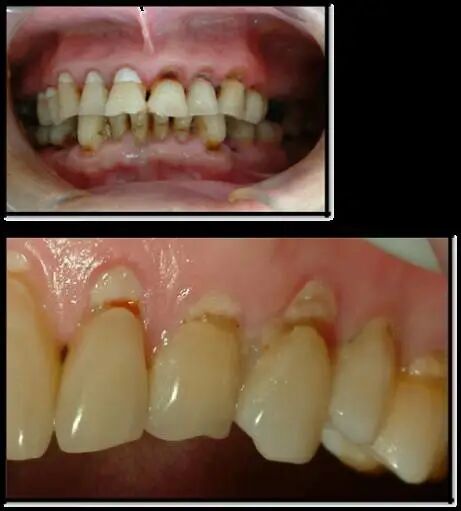

楔状缺损是发生在牙齿唇、颊面颈部的慢性硬组织缺损。典型的缺损由两个夹面组成,口大底小,呈楔形。楔状缺损往往发生在同一患者的多颗牙,一般上颌牙重于下颌牙,口角附近的牙多于其他区域的牙。

2、好发于第一前磨牙,位于牙弓弧度最突出处,刷牙时受力大,次数多,缺损一般有牙龈退缩。随着缺损越来越大,出现敏感甚至自发痛症状,严重者可导致牙齿折断。